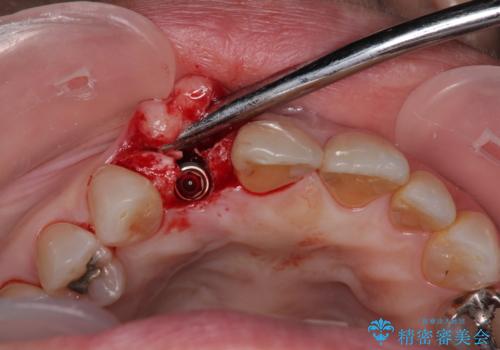

仮歯を事前に用意し、インプラント埋入時に即日で仮歯を装着する、即時荷重インプラントの計画で治療を進めて行くこととしました。

新幹線や飛行機を利用しても来院であり、極力来院回数を減らしたり、東京に用事があるタイミングに合わせてアポイントを調整したりと、負担が少なくなるようにして治療を進めて行きました。

来院間隔があいたため、予定よりも長くなりましたが、大きなトラブルもなく、外科処置は1回のみ、最小の来院数で無事に治療を終えることができました。